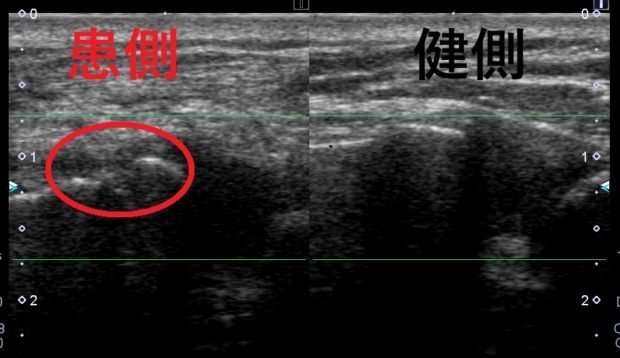

エコー画像で観察したものでは、赤丸で囲った部分の

骨の連続性が途絶えているのがわかります。

精査を行ったところ左鎖骨骨折という診断でした。